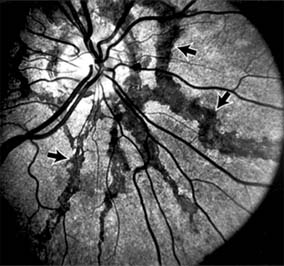

TRAUMATIC MACULOPATHY

Blunt trauma to the anterior segment of the eye may cause a contrecoup injury to the retina called commotio retinae. The retina develops a gray-white color that affects primarily the outer retina and may be confined to the macular area (Berlin's edema) or may involve extensive areas of the peripheral retina. The retinal whitening in the macular area may clear completely, or impairment of central vision may be permanent and associated with a pigmented retinal scar (Figure 10-13) or a macular hole. Trauma similar to that which causes Berlin's edema may also cause choroidal rupture with subretinal hemorrhage and permanent central vision loss.

Figure 10-13

Figure 10-13: Traumatic choroidal rupture resulting in pigmented scar. A choroidal vessel (arrow) is visible through the scar.